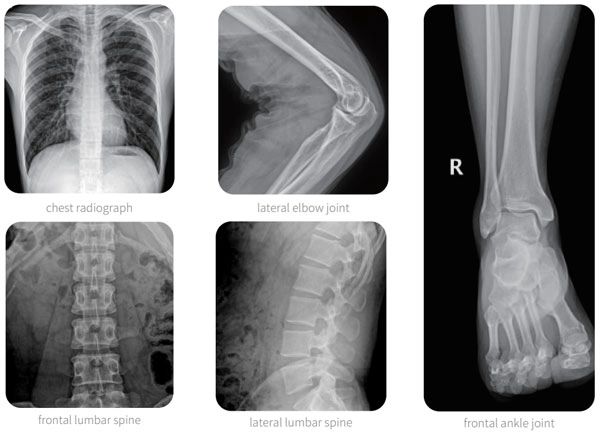

High definition image, Easy for clinical.

High definition image, Easy for clinical:

• High quality portable FPD,outstanding acquisition conversion performance, the sharp clinical image can be guaranteed.It can realize digital radiography of all human body parts friendly, like head, limbs, chest, spine lumber and so on.

Enhanced image clarity delivers diagnosis precision:

• High power, high frequency and high voltage generator: PLX5200A 50kW version is equipped with 50KW split high-frequency and high-voltage generator, with stable high-voltage output, high-quality X-ray can be stably output with the x-ray tube, which meet the needs of a variety of positions and provide guarantee for clear clinical images.

• Excellent wireless detector: PLX5200A 50kW version adopts 14*17 inches wireless detector, which has wide field of vision and convenient positioning;with high image clarity and fine imaging.The l6 bit gray scale can clearly show the radiation position tissue details of the exposure site, with high image differentiation and accurate clinical diagnosis.